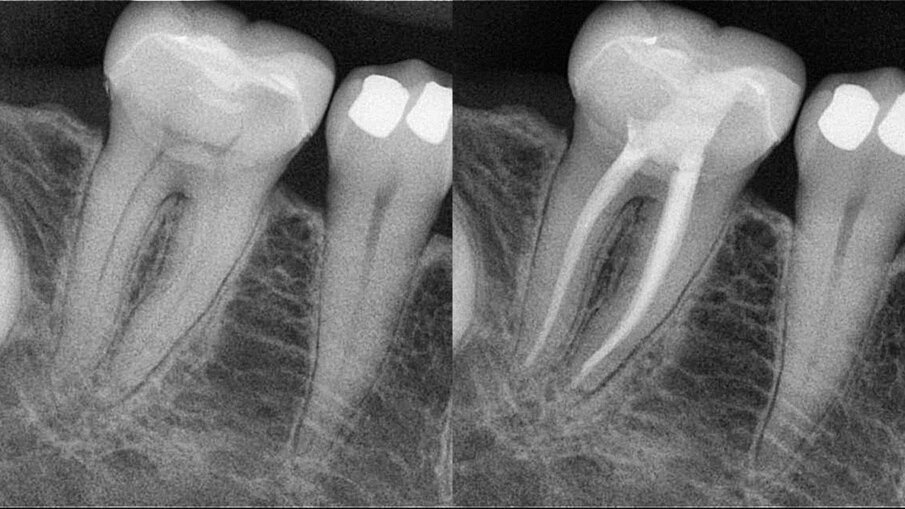

In both cases presented, the root canal therapy was necessary due to an irreversible pulpitis process affecting the respective teeth (Figs. 4a–5b). Both were approached minimally invasively, starting from the endodontic access cavity preparation and finishing with the post endodontic core build-up.

Figs. 4a–d: Root canal therapy performed through a conservative access cavity in a tooth #37 with severe curvatures at the mesial root. The root canal obturation was performed by the hydraulic compaction technique.

One of the most challenging situations when working through conservative openings is the root canal obturation step. The lack of straight line access, compromised visibility and a reduced opening to properly clean the pulp chamber are factors to take into consideration.15 The physical properties of calcium silicate-based endodontic sealers allow clinicians to overcome those challenging aspects. The relatively easy obturation technique, flowability and easy process of cleaning the pulp chamber provide the necessary means for proceeding with the endodontic therapy as conservatively as possible without compromising the prognosis. In the clinical cases presented, the Aurum Blue system (Meta Biomed) was used for the root canal shaping and the calcium silicate-based endodontic sealer CeraSeal (Meta Biomed) was used, applied with the cold hydraulic compaction technique (see video below).